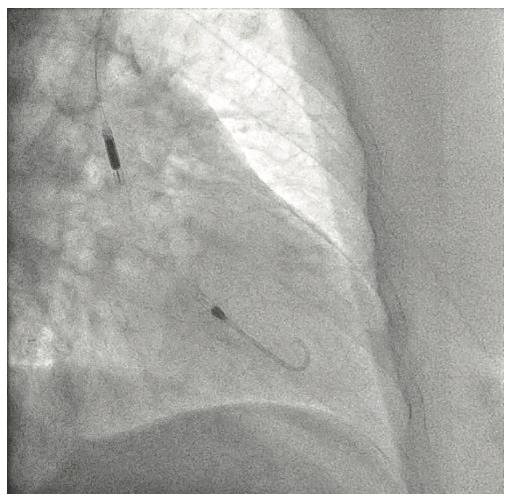

Following the Perclose placement, we upsized to a 14 Fr x 13 cm Cook Medical sheath (Figures 7-8), and through that, advanced a JR catheter into the ventricle and switched out for the Impella 2.5 device (Figure 9). A JR4 and eventually, an Amplatz right (AR) mod, was used from the right ulnar to engage the RCA, and an Extra Backup (EBU) 3.5, 7 Fr (Medtronic) was used from the groin. Dual angiography was performed (Figure 10). Once the activated clotting time (ACT) was >300 seconds, the ramus was wired with a Marvel wire (Boston Scientific). We attempted to cross the LAD CTO using a Corsair (Asahi Intecc) and a Pilot 200 (Abbott Vascular). The Pilot 200 crossed, but it appeared to be in the diagonal and could not be redirected down the LAD. A Gaia second (Asahi Intecc) was able to cross into the LAD (Figure 11), and at that point, was switched out via the Corsair for a workhorse wire, a Runthrough (Terumo). An 0.9 laser (Spectranetics) was used perform laser atherectomy for a minute and a half on the LAD (Figure 12), but we could not get the catheter across. However, this allowed us to advance a balloon across the lesion and we predilated with a 1.5 mm x 20 mm Mini Trek (Abbott Vascular) and then a 2.0 mm x 20 mm balloon. The same 2.0 mm x 20 mm balloon was used in the ramus. A 2.5 mm x 15 mm AngioSculpt (Philips) was used to predilate the LAD, but on its return, the AngioSculpt became stuck and would not come back. We got it partially into the guide and then the shaft broke. We had part of the catheter in the guide and part of it in the coronary (the left main). We initiated a series of procedures to remove the AngioSculpt, first attempting use of a GuideLiner (Vascular Solutions) to envelope the balloon, but this was unsuccessful (Figure 13). The GuideLiner kept pushing the device further out. We tried trapping it; that was also unsuccessful. We were able to get a Mini Trek balloon distal, thinking it could be inflated and pulled back; that did not work. We then put the 4 wires down, wrapped the wires around and pulled back, getting it partially in the guide, but we could not get it all the way in. We got a Mini Trek down, used the GuideLiner to put a 2.0 down, and attempted an anchor technique that did not work, but this time, when we pulled the Mini Trek 2.0 back, it dislodged the balloon. The AngioSculpt was able to come in the guide and was removed without losing wire position. We rewired the ramus, performed dilation of the LAD and ramus with a 2.5 mm noncompliant balloon, and performed intravascular ultrasound (IVUS). The LAD was about 2.75 mm2 distally and the ramus was 3.0 mm2, with the left main being approximately 3.75 mm2. A double kissing (DK) crush technique was used with a 2.75 mm x 38 mm Synergy stent (Boston Scientific) to the LAD and 3.0 mm x 24 mm Synergy to the ramus; then we used proximal optimization technique (POT) with a 3.75 mm NC balloon (Medtronic) and a final kiss with 3.0 mm x 20 mm NC balloons (Figures 14-17). IVUS was used to confirm that the stents were well apposed. The Impella device was weaned and removed, keeping the sheath in. From the groin sheath, a balloon was advanced into the left subclavian and we did a dry close. We inflated an 8.0 mm x 40 mm balloon at 3 atmospheres (nominal is 6 atmospheres) (Figure 18). Once the pressure tracing from the axillary sheath side arm dropped, we were able to remove the sheath and then completed the Perclose. There was some slight track ooze (Figure 19). Therefore, we performed two 5-minute inflations with the 8.0 mm x 40 mm balloon at 3 atmospheres (nominal is 6 atmospheres), and there was complete resolution of the track ooze. No extravasation was noted (Figures 20-21). The ulnar sheath was sutured in, we made sure there were no issues overnight, and the patient was discharged the following morning.

- If prolonged hemodynamic support is needed, the Impella sheath should be sutured and secured before the patient leaves the cath lab. In regard to the Perclose sutures, we recommend clamping the sutures with a hemostat and wrapping them with a sterile towel covered with sterile Tegaderm. The towels are then stuck to the chest wall1 (Figure 24).